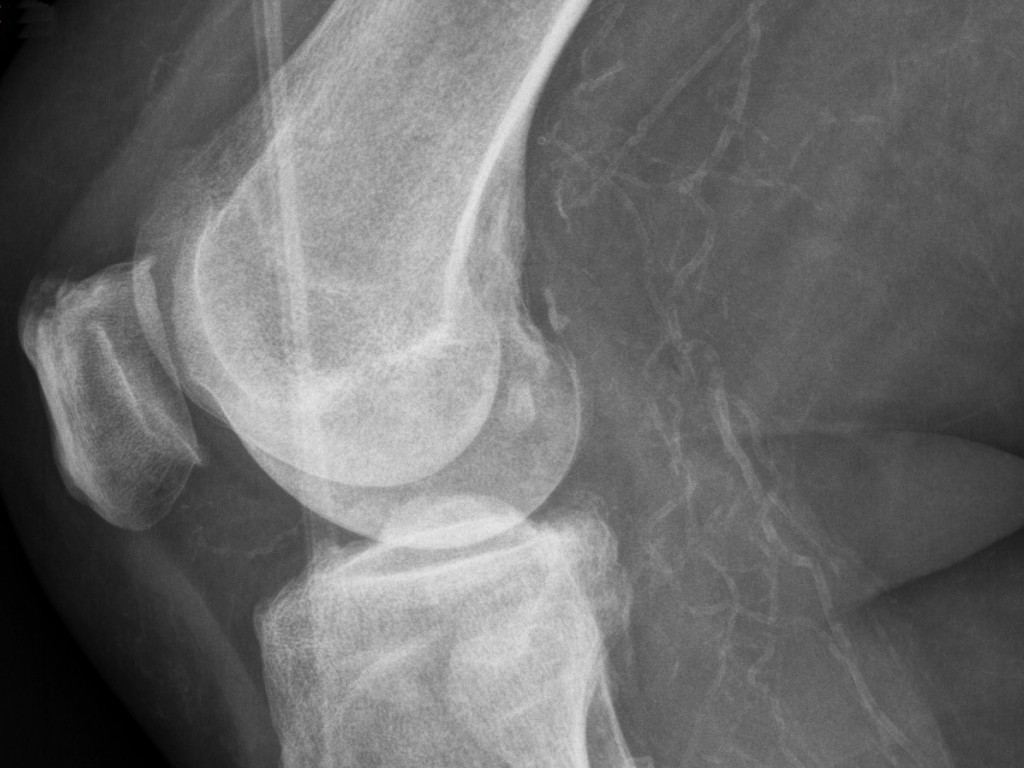

Atypical calciphylaxis cutisNaast

bovengenoemde klassieke vorm van calciphylaxis is er in een aantal

case-reports ook een

atypische variant beschreven, waarbij er ook arteriën

dicht gaan zitten t.g.v. calciumdeposities in de vaten, maar niet op basis

van nierinsufficiëntie en hyperparathyreoïdie. Bij een deel van deze

patiënten blijkt dit geassocieerd te zijn met het voorschrijven van

acenocoumarol. In de literatuur is dit terug te vinden onder de term

acenoumarol- of

warfarin-induced calciphylaxis. Het werkingsmechanisme ervan

Atypische calciphylaxis cutis wordt in de case-reports gedefinieerd als

necrose van de huid met zeer pijnlijke ulcera veroorzaakt afsluiting van

arterietakjes door uitgebreide calciumdeposities in de vaatwand

(histologisch en radiografisch aangetoond), maar bij afwezigheid van

nierinsufficiëntie en hyperparathyreoïdie (ureum, kreatinine, PTH, proteïne

C en proteïne S normaal). Het is echter moeilijk om deze entiteit 'atypische

calciphylaxis cutis' af te grenzen van gewone aderverkalking

(atherosclerose) die optreedt bij de bekende risicogroepen (overgewicht,

diabetes, hypertensie, roken, hypercholesterolemie).

![Atypical calciphylaxis (click on photo to enlarge) [source: www.huidziekten.nl] Atypical calciphylaxis](../../../images/calciphylaxis-cutis-atypical-3z.jpg) |

![Atypical calciphylaxis (click on photo to enlarge) [source: www.huidziekten.nl] Atypical calciphylaxis](../../../images/calciphylaxis-cutis-atypical-4z.jpg) |

| atypical calciphylaxis |

atypical calciphylaxis |